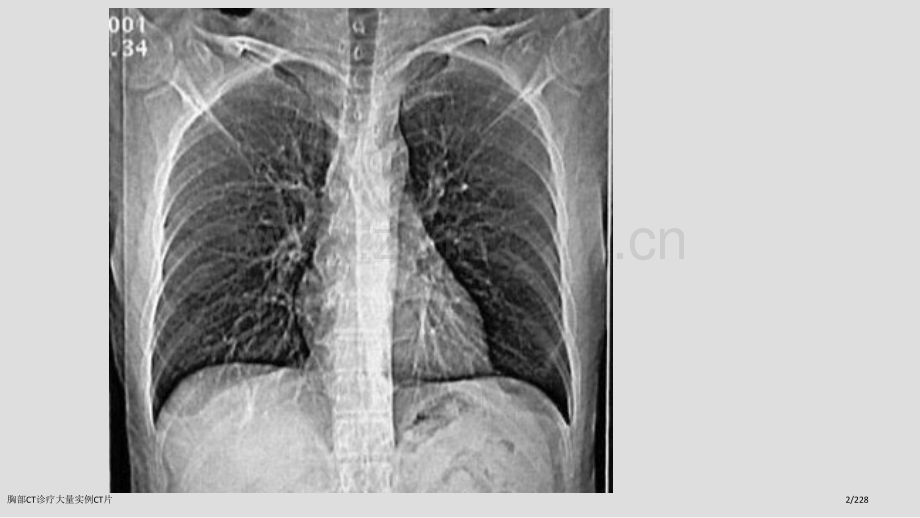

胸胸 部部 CT CT 诊诊 断断第一节第一节 胸部胸部CTCT检验检验一、胸部一、胸部CTCT扫描方法扫描方法(一)普通扫描(一)普通扫描 (平扫(平扫 plain CT scan plain CT scan)胸部CT诊疗大量实例CT片1/228胸部CT诊疗大量实例CT片2/228胸部CT诊疗大量实例CT片3/228胸部CT诊疗大量实例CT片4/228(二)增强扫描(二)增强扫描(contrast enhancement,CE)1.注药方法注药方法 团注法团注法 (bolus injection)静滴法静滴法 2.扫描程序扫描程序 静态静态CT扫描扫描 动态动态CT扫描(扫描(dynamic CT scan)胸部CT诊疗大量实例CT片5/228胸部CT诊疗大量实例CT片6/228 (三)特殊扫描(三)特殊扫描 1.薄层扫描薄层扫描 2.高分辨率高分辨率CT扫描扫描 (High resolution CT,HRCT)3.CT血管造影血管造影 (CT angiography,CTA)4.心电门控扫描心电门控扫描胸部CT诊疗大量实例CT片7/228胸部CT诊疗大量实例CT片8/228胸部CT诊疗大量实例CT片9/228胸部CT诊疗大量实例CT片10/228胸部CT诊疗大量实例CT片11/228胸部CT诊疗大量实例CT片12/228胸部CT诊疗大量实例CT片13/228二、二、CT对胸部疾病诊疗价值与程度对胸部疾病诊疗价值与程度(一)诊疗价值(一)诊疗价值 1.肺部小病灶与早期病变肺部小病灶与早期病变 2.咯血查因咯血查因 3.肺不张、肺实变肺不张、肺实变 4.肺肿瘤分期肺肿瘤分期 5.肺弥漫性病变肺弥漫性病变 6.肺气肿诊疗及功效评价肺气肿诊疗及功效评价 7.肺血管性病变肺血管性病变 8.胸水查因胸水查因胸部CT诊疗大量实例CT片14/228(二)影响(二)影响CT检出与诊疗原因检出与诊疗原因 (主要为常规(主要为常规CT)1.运动伪影运动伪影 2.部分容积效应部分容积效应 3.层厚与层间距层厚与层间距 4.大量胸水大量胸水 5.一病多像一病多像,一像多病一像多病胸部CT诊疗大量实例CT片15/228胸部CT诊疗大量实例CT片16/228胸部CT诊疗大量实例CT片17/228胸部CT诊疗大量实例CT片18/228三、胸部正常三、胸部正常CT解剖解剖(一)窗技术(一)窗技术 1.纵隔窗纵隔窗:窗位窗位3060Hu,窗宽窗宽300500Hu 2.肺窗:肺窗:窗位窗位-700-400Hu,窗宽窗宽10001500Hu(二)纵隔(二)纵隔(mediastinum)(三)肺(三)肺(lung)胸部CT诊疗大量实例CT片19/228胸部CT诊疗大量实例CT片20/228胸部CT诊疗大量实例CT片21/228胸部CT诊疗大量实例CT片22/228胸部CT诊疗大量实例CT片23/228胸部CT诊疗大量实例CT片24/228胸部CT诊疗大量实例CT片25/228胸部CT诊疗大量实例CT片26/228胸部CT诊疗大量实例CT片27/228胸部CT诊疗大量实例CT片28/228胸部CT诊疗大量实例CT片29/228胸部CT诊疗大量实例CT片30/228胸部CT诊疗大量实例CT片31/228胸部CT诊疗大量实例CT片32/228胸部CT诊疗大量实例CT片33/228胸部CT诊疗大量实例CT片34/228胸部CT诊疗大量实例CT片35/228胸部CT诊疗大量实例CT片36/228胸部CT诊疗大量实例CT片37/228胸部CT诊疗大量实例CT片38/228胸部CT诊疗大量实例CT片39/228胸部CT诊疗大量实例CT片40/228胸部CT诊疗大量实例CT片41/228胸部CT诊疗大量实例CT片42/228胸部CT诊疗大量实例CT片43/228胸部CT诊疗大量实例CT片44/228胸部CT诊疗大量实例CT片45/228胸部CT诊疗大量实例CT片46/228胸部CT诊疗大量实例CT片47/228胸部CT诊疗大量实例CT片48/228胸部CT诊疗大量实例CT片49/228胸部CT诊疗大量实例CT片50/228第二节第二节 肺部疾病肺部疾病CT诊疗诊疗一、先天性疾病一、先天性疾病 1.肺隔离症(肺隔离症(pulmonary sequestration)某一肺段和正常肺组织及气管和支某一肺段和正常肺组织及气管和支气管树相互分离,无呼吸功效,血供来气管树相互分离,无呼吸功效,血供来自主动脉系统,分叶内型和叶外型两类。自主动脉系统,分叶内型和叶外型两类。胸部CT诊疗大量实例CT片51/228CTCT表现:表现:v部位:两下肺、脊柱旁。部位:两下肺、脊柱旁。v形态:囊实性或囊性或实性,邻近肺形态:囊实性或囊性或实性,邻近肺 野斑片状影。野斑片状影。v血供:体循环,病灶内血管异常。血供:体循环,病灶内血管异常。判别诊疗:判别诊疗:支气管源性囊肿、肺脓肿、先天性膈疝。支气管源性囊肿、肺脓肿、先天性膈疝。胸部CT诊疗大量实例CT片52/228胸部CT诊疗大量实例CT片53/228胸部CT诊疗大量实例CT片54/228胸部CT诊疗大量实例CT片55/228胸部CT诊疗大量实例CT片56/2282.支气管囊肿(支气管囊肿(bronchogenic cyst)为支气管先天发育异常,依据组为支气管先天发育异常,依据组织学起源可分为支气管囊肿和支气管肺织学起源可分为支气管囊肿和支气管肺囊肿囊肿(pulmonary bronchogenic cyst)。CT表现表现:v部位:纵隔与肺任何部位,多见于部位:纵隔与肺任何部位,多见于 气气 管隆突管隆突5cm范围内。范围内。v形态:圆形、椭圆形、边缘锐利,壁形态:圆形、椭圆形、边缘锐利,壁 菲薄。菲薄。v密度:均匀,可有出血和液气平,壁密度:均匀,可有出血和液气平,壁 可强化。可强化。胸部CT诊疗大量实例CT片57/228胸部CT诊疗大量实例CT片58/228胸部CT诊疗大量实例CT片59/228胸部CT诊疗大量实例CT片60/228胸部CT诊疗大量实例CT片61/228胸部CT诊疗大量实例CT片62/228胸部CT诊疗大量实例CT片63/228胸部CT诊疗大量实例CT片64/228胸部CT诊疗大量实例CT片65/228胸部CT诊疗大量实例CT片66/228二、支气管扩张症(二、支气管扩张症(bronchiectasis)病因:先天性或后天性病因:先天性或后天性 病理:肉眼观,支气管呈柱状、囊状、静病理:肉眼观,支气管呈柱状、囊状、静 脉曲张状或混合状扩张。脉曲张状或混合状扩张。镜下观,粘膜柱状上皮呈急、慢性镜下观,粘膜柱状上皮呈急、慢性 炎性改变,伴弹力纤维、炎性改变,伴弹力纤维、平滑肌和软骨损害。平滑肌和软骨损害。胸部CT诊疗大量实例CT片67/228CTCT表现:表现:病变支气管壁增厚,管腔病变支气管壁增厚,管腔 扩大,形态多样。扩大,形态多样。1.1.柱状扩张柱状扩张:“:“双轨双轨”征、征、“印戒印戒”征。征。2.2.囊状扩张囊状扩张:葡萄串状、卷发样。葡萄串状、卷发样。3.3.曲张形扩张曲张形扩张:粗细不均囊柱状。粗细不均囊柱状。4.4.混合型混合型 合并粘液栓时合并粘液栓时,腔内可见棒状腔内可见棒状 或结节状软组织密度影或结节状软组织密度影,咳痰后可咳痰后可 消失,同时可见肺野内出血消失,同时可见肺野内出血,继发继发 感染等征象。感染等征象。胸部CT诊疗大量实例CT片68/228胸部CT诊疗大量实例CT片69/228胸部CT诊疗大量实例CT片70/228胸部CT诊疗大量实例CT片71/228胸部CT诊疗大量实例CT片72/228胸部CT诊疗大量实例CT片73/228胸部CT诊疗大量实例CT片74/228胸部CT诊疗大量实例CT片75/228胸部CT诊疗大量实例CT片76/228胸部CT诊疗大量实例CT片77/228胸部CT诊疗大量实例CT片78/228胸部CT诊疗大量实例CT片79/228三、肺感染性病变三、肺感染性病变 1.支气管肺炎支气管肺炎 支气管肺炎(支气管肺炎(bronchopneumonia)或小叶性肺炎(或小叶性肺炎(lobular pneumonia)病病 理:理:小支气管壁充血、水肿、间小支气管壁充血、水肿、间 质炎性细胞浸润,小叶渗出、质炎性细胞浸润,小叶渗出、实变、气肿或不张。实变、气肿或不张。CT表现:表现:两肺中下野中内带,支气管两肺中下野中内带,支气管 血管束增粗,沿其分布小斑血管束增粗,沿其分布小斑 片影及边缘含糊小结节影。片影及边缘含糊小结节影。胸部CT诊疗大量实例CT片80/228胸部CT诊疗大量实例CT片81/228胸部CT诊疗大量实例CT片82/228胸部CT诊疗大量实例CT片83/228胸部CT诊疗大量实例CT片84/228胸部CT诊疗大量实例CT片85/228胸部CT诊疗大量实例CT片86/2282.2.大叶性肺炎大叶性肺炎 大叶性肺炎(大叶性肺炎(lobar pneumonialobar pneumonia),),炎症累及整个肺叶,或呈肺段分布。炎症累及整个肺叶,或呈肺段分布。病理:充血期,病理:充血期,毛细血管充血,肺毛细血管充血,肺 泡内可有少许浆液性渗出。泡内可有少许浆液性渗出。红色肝样变期,红色肝样变期,渗出液中含渗出液中含 较多红细胞。较多红细胞。灰色肝样变期,灰色肝样变期,渗出液中含渗出液中含 大量白细胞。大量白细胞。消散期,消散期,渗出液溶解、吸收。渗出液溶解、吸收。胸部CT诊疗大量实例CT片87/228CTCT表现:表现:渗出期表现为磨玻璃样影;实变渗出期表现为磨玻璃样影;实变期呈叶、段实变,可见空气支气管期呈叶、段实变,可见空气支气管征,叶间裂可向外膨出;消散期则呈征,叶间裂可向外膨出;消散期则呈斑片状影。斑片状影。判别诊疗:判别诊疗:阻塞性肺炎,结核性大叶炎、阻塞性肺炎,结核性大叶炎、肺肿瘤(腺癌、肺泡癌或淋巴瘤)。肺肿瘤(腺癌、肺泡癌或淋巴瘤)。胸部CT诊疗大量实例CT片88/228胸部CT诊疗大量实例CT片89/228胸部CT诊疗大量实例CT片90/228胸部CT诊疗大量实例CT片91/2283.3.肺脓肿肺脓肿 肺脓肿(肺脓肿(lung abscesslung abscess),由化),由化脓性细菌引发肺坏死性炎性病变,脓性细菌引发肺坏死性炎性病变,分急性和慢性肺脓肿。分急性和慢性肺脓肿。病理:病理:细支气管阻塞,小血管炎性栓塞,细支气管阻塞,小血管炎性栓塞,肺组织坏死、液化,周围有纤维肺组织坏死、液化,周围有纤维 组织增生。组织增生。胸部CT诊疗大量实例CT片92/228CTCT表现:表现:急性期:大片密实影,中心密度较急性期:大片密实影,中心密度较低,空洞形成后,壁厚而含糊,内有液低,空洞形成后,壁厚而含糊,内有液平;慢性期:洞壁清楚,内壁多不规整,平;慢性期:洞壁清楚,内壁多不规整,增强扫描洞壁强化,支气管、肺血管于增强扫描洞壁强化,支气管、肺血管于脓肿边缘截断。脓肿边缘截断。判别诊疗:判别诊疗:结核空洞、癌性空洞结核空洞、癌性空洞胸部CT诊疗大量实例CT片93/228胸部CT诊疗大量实例CT片94/228胸部CT诊疗大量实例CT片95/228胸部CT诊疗大量实例CT片96/228胸部CT诊疗大量实例CT片97/228胸部CT诊疗大量实例CT片98/228 4.4.肺结核肺结核 肺结核(肺结核(pulmonary tuberculosispulmonary tuberculosis),由人型或牛型结核杆菌引发肺部慢性传由人型或牛型结核杆菌引发肺部慢性传染病。染病。病理:病理:渗出结核性肺泡炎,增殖渗出结核性肺泡炎,增殖结核性结节肉芽肿。继发改变:干酪样坏结核性结节肉芽肿。继发改变:干酪样坏死、液化、空洞、死、液化、空洞、播散;纤维化、钙化。播散;纤维化、钙化。胸部CT诊疗大量实例CT片99/228CT表现:表现:型:原发性肺结核型:原发性肺结核(primary tuberculosis)纵隔、肺门淋巴结增大,增强扫描纵隔、肺门淋巴结增大,增强扫描多呈环形强化。肺内原发灶呈片影或段、多呈环形强化。肺内原发灶呈片影或段、叶实变,内可见低密度坏死、空洞。叶实变,内可见低密度坏死、空洞。可合并叶或段不张。可合并叶或段不张。胸部CT诊疗大量实例CT片100/228胸部CT诊疗大量实例CT片101/228胸部CT诊疗大量实例CT片102/228胸部CT诊疗大量实例CT片103/228胸部CT诊疗大量实例CT片104/228胸部CT诊疗大量实例CT片105/228型:血行播散型肺结核型:血行播散型肺结核(acute miliary tuberculosis and chronic disseminated tuberculosis)急性血行播散型急性血行播散型,CT表现为双肺广泛表现为双肺广泛分布分布12mm小点状阴影小点状阴影,密度均匀密度均匀,边界边界清清,分布均匀分布均匀,与支气管走行无关与支气管走行无关,以以HRCT显示为佳。亚急性或慢性血行播散型显示为佳。亚急性或慢性血行播散型,病灶病灶大小不一大小不一,密度不均密度不均,可有钙化可有钙化,上中肺野分上中肺野分布为主。布为主。胸部CT诊疗大量实例CT片106/228胸部CT诊疗大量实例CT片107/228胸部CT诊疗大量实例CT片108/228胸部CT诊疗大量实例CT片109/228胸部CT诊疗大量实例CT片110/228胸部CT诊疗大量实例CT片111/228胸部CT诊疗大量实例CT片112/228型:继发性肺结核型:继发性肺结核(secondary pulmonary tuberculosis)肺尖后段、下叶背段常见,单发或多肺尖后段、下叶背段常见,单发或多 发腺泡结节状影,小叶、肺段或肺叶发腺泡结节状影,小叶、肺段或肺叶 实变。实变。病变密度不均,可见钙化、坏死、空病变密度不均,可见钙化、坏死、空 洞,纤维索条影。洞,纤维索条影。病灶邻近胸膜增厚。病灶邻近胸膜增厚。胸部CT诊疗大量实例CT片113/228胸部CT诊疗大量实例CT片114/228胸部CT诊疗大量实例CT片115/228胸部CT诊疗大量实例CT片116/228胸部CT诊疗大量实例CT片117/228v caseous pneumonia:caseous pneumonia:大叶性实变,可见空气支气管征,大叶性实变,可见空气支气管征,小空洞小空洞,下肺野可见支气管播散灶。下肺野可见支气管播散灶。v tuberculoma:tuberculoma:类圆形结节,可呈浅分叶,边缘类圆形结节,可呈浅分叶,边缘 清楚,直径清楚,直径2 24cm4cm,内可有坏死,结,内可有坏死,结 节状、斑点状或层状钙化,周围常见节状、斑点状或层状钙化,周围常见 卫星灶,增强扫描结节多呈环形强化。卫星灶,增强扫描结节多呈环形强化。胸部CT诊疗大量实例CT片118/228胸部CT诊疗大量实例CT片119/228胸部CT诊疗大量实例CT片120/228胸部CT诊疗大量实例CT片121/228胸部CT诊疗大量实例CT片122/228胸部CT诊疗大量实例CT片123/228胸部CT诊疗大量实例CT片124/228胸部CT诊疗大量实例CT片125/228胸部CT诊疗大量实例CT片126/228型:胸膜炎型(结核性胸膜炎)型:胸膜炎型(结核性胸膜炎)可单独或与肺部结核合并存在,可单独或与肺部结核合并存在,表现为胸水,胸膜增厚或胸膜结节。表现为胸水,胸膜增厚或胸膜结节。肺结核判别诊疗:肺结核判别诊疗:其它感染其它感染 肺癌肺癌 炎性假瘤炎性假瘤 肉芽肿肉芽肿胸部CT诊疗大量实例CT片127/228胸部CT诊疗大量实例CT片128/228胸部CT诊疗大量实例CT片129/228胸部CT诊疗大量实例CT片130/228胸部CT诊疗大量实例CT片131/228胸部CT诊疗大量实例CT片132/228肺癌肺癌原发性支气管肺癌原发性支气管肺癌(primary bronchogenic carcinomaprimary bronchogenic carcinoma)是呼吸系统常见病,在全身恶性肿瘤是呼吸系统常见病,在全身恶性肿瘤中居第二位。中居第二位。病理:病理:肺癌起源于支气管上皮,腺体或细肺癌起源于支气管上皮,腺体或细 支气管肺泡上皮。支气管肺泡上皮。组织学分型:组织学分型:小细胞肺癌和非小细胞肺癌小细胞肺癌和非小细胞肺癌 (鳞癌、腺癌、大细胞未分化(鳞癌、腺癌、大细胞未分化 癌、复合癌)。癌、复合癌)。按发生部位分:按发生部位分:中心型、外围型、细支气中心型、外围型、细支气 管肺泡癌。管肺泡癌。胸部CT诊疗大量实例CT片133/228CTCT表现表现:(1 1)中心型肺癌:)中心型肺癌:v 肺门肿块,常伴肺不张或阻塞性肺炎肺门肿块,常伴肺不张或阻塞性肺炎v 支气管异常支气管异常v 淋巴结转移及血行转移淋巴结转移及血行转移v 纵隔侵犯纵隔侵犯胸部CT诊疗大量实例CT片134/228胸部CT诊疗大量实例CT片135/228胸部CT诊疗大量实例CT片136/228胸部CT诊疗大量实例CT片137/228胸部CT诊疗大量实例CT片138/228胸部CT诊疗大量实例CT片139/228左上肺非特异性炎症左上肺非特异性炎症胸部CT诊疗大量实例CT片140/228(2 2)周围型肺癌)周围型肺癌v 肺外周结节,多呈分叶状,可有细短肺外周结节,多呈分叶状,可有细短 毛刺。毛刺。v 结节密度多不均匀,可有空泡征,支结节密度多不均匀,可有空泡征,支 气管气象,坏死、空洞、少数有钙化。气管气象,坏死、空洞、少数有钙化。v 血管纠集、细支气管截断。血管纠集、细支气管截断。v 胸膜牵引征胸膜牵引征v 增强扫描,增强扫描,CTCT值增加多在值增加多在20Hu20Hu以上。以上。v 转移征象转移征象胸部CT诊疗大量实例CT片141/228胸部CT诊疗大量实例CT片142/228胸部CT诊疗大量实例CT片143/228胸部CT诊疗大量实例CT片144/228胸部CT诊疗大量实例CT片145/228胸部CT诊疗大量实例CT片146/228胸部CT诊疗大量实例CT片147/228胸部CT诊疗大量实例CT片148/228胸部CT诊疗大量实例CT片149/228胸部CT诊疗大量实例CT片150/228胸部CT诊疗大量实例CT片151/228胸部CT诊疗大量实例CT片152/228胸部CT诊疗大量实例CT片153/228(3 3)细支气管肺泡癌)细支气管肺泡癌v 结节型:同周围型肺癌结节型:同周围型肺癌v 弥漫型:双肺弥漫分布腺胞结弥漫型:双肺弥漫分布腺胞结 节,可融合。节,可融合。v 实变型(肺炎型):肺段或叶实变型(肺炎型):肺段或叶 实变,常合并腺泡结节。实变,常合并腺泡结节。胸部CT诊疗大量实例CT片154/228胸部CT诊疗大量实例CT片155/228胸部CT诊疗大量实例CT片156/228胸部CT诊疗大量实例CT片157/228胸部CT诊疗大量实例CT片158/228胸部CT诊疗大量实例CT片159/228胸部CT诊疗大量实例CT片160/228胸部CT诊疗大量实例CT片161/228胸部CT诊疗大量实例CT片162/228(4 4)几个特殊类型肺癌:)几个特殊类型肺癌:肺上沟癌(肺上沟癌(Superior sulcus carcinoma Superior sulcus carcinoma Pancoast tumor Pancoast tumor)纵隔型肺癌纵隔型肺癌 肺炎型肺癌肺炎型肺癌 重复癌重复癌胸部CT诊疗大量实例CT片163/228胸部CT诊疗大量实例CT片164/228胸部CT诊疗大量实例CT片165/228胸部CT诊疗大量实例CT片166/228胸部CT诊疗大量实例CT片167/228胸部CT诊疗大量实例CT片168/228胸部CT诊疗大量实例CT片169/228胸部CT诊疗大量实例CT片170/228胸部CT诊疗大量实例CT片171/228胸部CT诊疗大量实例CT片172/228胸部CT诊疗大量实例CT片173/228胸部CT诊疗大量实例CT片174/228胸部CT诊疗大量实例CT片175/228第三节第三节 纵隔疾病纵隔疾病CTCT诊疗诊疗一、胸内甲状腺一、胸内甲状腺(intrathoracic thyroid glandintrathoracic thyroid gland)病因:病因:甲状腺肿、腺瘤、囊肿、癌甲状腺肿、腺瘤、囊肿、癌CTCT表现:表现:位置:位置:前上纵隔,气管和胸骨间,可前上纵隔,气管和胸骨间,可 推压气管,上与甲状腺相连。推压气管,上与甲状腺相连。密度:密度:较高、常有囊变、钙化、强化较高、常有囊变、钙化、强化 显著。显著。胸部CT诊疗大量实例CT片176/228胸部CT诊疗大量实例CT片177/228胸部CT诊疗大量实例CT片178/228二、胸腺增生与胸腺瘤二、胸腺增生与胸腺瘤(一)正常胸腺(一)正常胸腺 位于前上纵隔,主动脉弓前,位于前上纵隔,主动脉弓前,呈三角形,新月形或箭头状,呈三角形,新月形或箭头状,2020岁以岁以后逐步委缩,为脂肪替换。后逐步委缩,为脂肪替换。正常胸腺大小;正常胸腺大小;1 1月月1414岁厚岁厚度度22mm22mm;厚度与主动脉弓直径之比:;厚度与主动脉弓直径之比:1 1岁以内岁以内1.81.8,1 16 6岁岁1.21.2,6 61414岁岁0.90.9。胸部CT诊疗大量实例CT片179/228胸部CT诊疗大量实例CT片180/228胸部CT诊疗大量实例CT片181/228(二)胸腺增生(二)胸腺增生(thymic hyperplasiathymic hyperplasia)弥漫性增生弥漫性增生结节状增生结节状增生胸部CT诊疗大量实例CT片182/228胸部CT诊疗大量实例CT片183/228胸部CT诊疗大量实例CT片184/228胸部CT诊疗大量实例CT片185/228(三)胸腺瘤(三)胸腺瘤(thymomathymoma)病病 理:理:上皮细胞为主型、淋巴细胞为主型上皮细胞为主型、淋巴细胞为主型 和混合型。和混合型。CTCT表现:表现:分非侵袭性和侵袭性胸腺瘤。前上分非侵袭性和侵袭性胸腺瘤。前上 纵隔内结节影,向一侧或两侧突出,纵隔内结节影,向一侧或两侧突出,边界清楚密度较均匀,可有囊变和边界清楚密度较均匀,可有囊变和 钙化,增强扫描显著强化。侵袭性钙化,增强扫描显著强化。侵袭性 者弥漫浸润于大血管间,心包和胸者弥漫浸润于大血管间,心包和胸 腔积液。腔积液。判别诊疗:判别诊疗:胸腺增生与胸腺瘤胸腺增生与胸腺瘤 畸胎瘤畸胎瘤 淋巴瘤淋巴瘤胸部CT诊疗大量实例CT片186/228胸部CT诊疗大量实例CT片187/228胸部CT诊疗大量实例CT片188/228胸部CT诊疗大量实例CT片189/228胸部CT诊疗大量实例CT片190/228胸部CT诊疗大量实例CT片191/228三、畸胎瘤(三、畸胎瘤(teratomateratoma)病理:病理:起源于原始生殖细胞,一个或多起源于原始生殖细胞,一个或多 种胚胎成份,有囊性和实质性种胚胎成份,有囊性和实质性CTCT表现:表现:前纵隔,边缘光滑之厚壁囊性肿块,前纵隔,边缘光滑之厚壁囊性肿块,含脂肪、脂液分层、钙化、骨骼或牙齿、含脂肪、脂液分层、钙化、骨骼或牙齿、囊性畸胎瘤壁常呈蛋壳状钙化。囊性畸胎瘤壁常呈蛋壳状钙化。胸部CT诊疗大量实例CT片192/228胸部CT诊疗大量实例CT片193/228胸部CT诊疗大量实例CT片194/228四、淋巴瘤(四、淋巴瘤(lymphoma)病理:病理:淋巴结或结外淋巴组织,分淋巴结或结外淋巴组织,分 Hodgkin disease,HD和和non Hodgkin lymphoma,NHLCT表现表现:纵隔肺门多组淋巴结肿大,可纵隔肺门多组淋巴结肿大,可融合成团,压迫或侵犯纵隔结构。融合成团,压迫或侵犯纵隔结构。偶有坏死与钙化,强化程度较低。偶有坏死与钙化,强化程度较低。判别诊疗:判别诊疗:淋巴结结核淋巴结结核 结节病结节病胸腺瘤胸腺瘤 转移瘤转移瘤胸部CT诊疗大量实例CT片195/228胸部CT诊疗大量实例CT片196/228胸部CT诊疗大量实例CT片197/228胸部CT诊疗大量实例CT片198/228胸部CT诊疗大量实例CT片199/228胸部CT诊疗大量实例CT片200/228胸部CT诊疗大量实例CT片201/228胸部CT诊疗大量实例CT片202/228胸部CT诊疗大量实例CT片203/228胸部CT诊疗大量实例CT片204/228胸部CT诊疗大量实例CT片205/228五、心包囊肿(五、心包囊肿(pericardial cyst)多为单房多为单房,可发生于心包任何可发生于心包任何 部位,以心膈区多见。部位,以心膈区多见。常位于右心常位于右心 膈角区,呈边缘清楚锐利囊状影。膈角区,呈边缘清楚锐利囊状影。判别诊疗:判别诊疗:心包憩室心包憩室 支气管囊肿支气管囊肿胸部CT诊疗大量实例CT片206/228胸部CT诊疗大量实例CT片207/228胸部CT诊疗大量实例CT片208/228胸部CT诊疗大量实例CT片209/228胸部CT诊疗大量实例CT片210/228胸部CT诊疗大量实例CT片211/228胸部CT诊疗大量实例CT片212/228 六、神经源性肿瘤六、神经源性肿瘤(neurogenic tumor)是后纵隔最常见肿瘤,多起源于肋是后纵隔最常见肿瘤,多起源于肋间神经内侧段或椎旁交感神经链。分神经间神经内侧段或椎旁交感神经链。分神经纤维瘤、神经鞘瘤、神经节细胞瘤、神经纤维瘤、神经鞘瘤、神经节细胞瘤、神经母细胞瘤等。母细胞瘤等。CT表现表现:后纵隔脊柱旁类圆形肿块,密度均匀,后纵隔脊柱旁类圆形肿块,密度均匀,部分呈哑铃状,椎间孔扩大,肋骨头和脊部分呈哑铃状,椎间孔扩大,肋骨头和脊椎受压,良性者边缘锐利,恶性者边缘不椎受压,良性者边缘锐利,恶性者边缘不清,侵蚀骨骼,增强扫描呈中等强化。清,侵蚀骨骼,增强扫描呈中等强化。胸部CT诊疗大量实例CT片213/228胸部CT诊疗大量实例CT片214/228胸部CT诊疗大量实例CT片215/228胸部CT诊疗大量实例CT片216/228胸部CT诊疗大量实例CT片217/228胸部CT诊疗大量实例CT片218/228胸部CT诊疗大量实例CT片219/228胸部CT诊疗大量实例CT片220/228胸部CT诊疗大量实例CT片221/228胸部CT诊疗大量实例CT片222/228胸部CT诊疗大量实例CT片223/228胸部CT诊疗大量实例CT片224/228胸部CT诊疗大量实例CT片225/228胸部CT诊疗大量实例CT片226/228胸部CT诊疗大量实例CT片227/228The endThe end谢谢 谢谢 !胸部CT诊疗大量实例CT片228/228